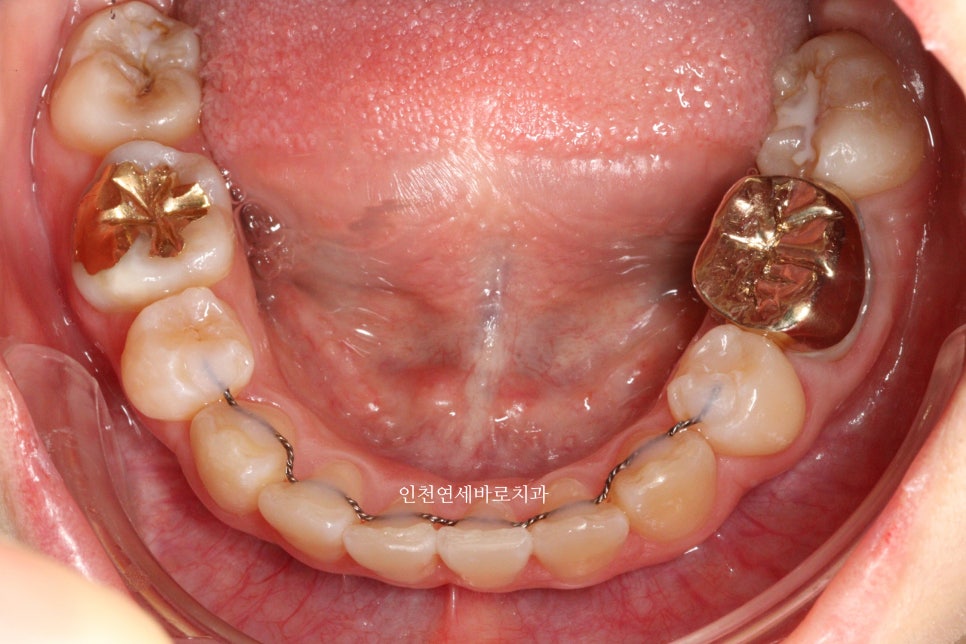

변화모습입니다.

장치의 제작이 한달이나 걸리기 때문에 3/30이 처음 교정치료를 시작했던 날입니다.

약 3개월의 변화모습입니다.